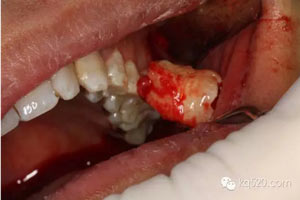

圖10. 28牙齒被完整取出來(lái)。

圖11.取出來(lái)的28牙齒。